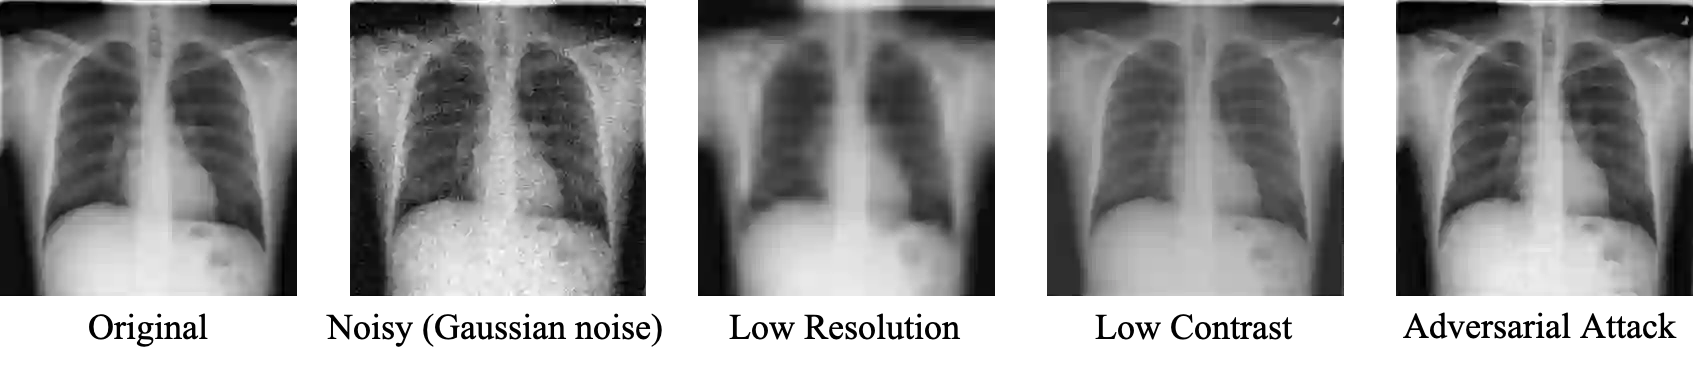

While deep learning models have achieved remarkable success across a range of medical image analysis tasks, deployment of these models in real clinical contexts requires that they be robust to variability in the acquired images. While many methods apply predefined transformations to augment the training data to enhance test-time robustness, these transformations may not ensure the model's robustness to the diverse variability seen in patient images. In this paper, we introduce a novel three-stage approach based on transformers coupled with conditional diffusion models, with the goal of improving model robustness to the kinds of imaging variability commonly encountered in practice without the need for pre-determined data augmentation strategies. To this end, multiple image encoders first learn hierarchical feature representations to build discriminative latent spaces. Next, a reverse diffusion process, guided by the latent code, acts on an informative prior and proposes prediction candidates in a generative manner. Finally, several prediction candidates are aggregated in a bi-level aggregation protocol to produce the final output. Through extensive experiments on medical imaging benchmark datasets, we show that our method improves upon state-of-the-art methods in terms of robustness and confidence calibration. Additionally, we introduce a strategy to quantify the prediction uncertainty at the instance level, increasing their trustworthiness to clinicians using them in clinical practice.